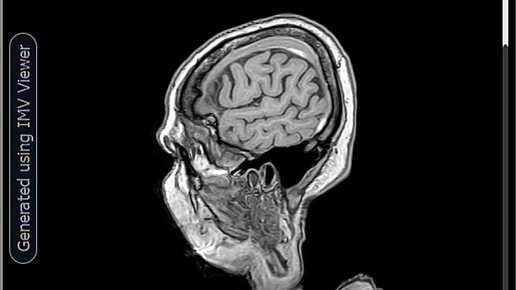

МРТ-Хронические субдуральные гематомы